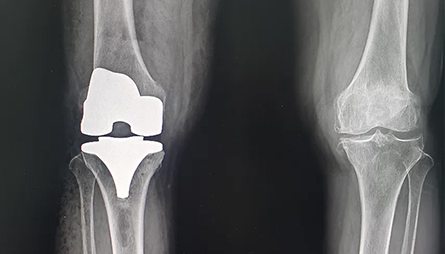

患者:李某、女、71岁。主诉:双膝关节疼痛伴活动受限十余年。现病史:患者于十年前无明显诱因下出现双膝关节酸胀疼痛,以右膝关节为主,活动时加重,尤其以上下楼梯、下蹲时为明显,休息时缓解,疼痛程度中等,尚能忍受,无他处放射痛,呈现起始疼痛→缓解→疼痛的特点,疼痛时患者无咯血、胸闷、心悸,无腹痛、恶心及呕吐,无大汗淋漓,无畏寒发热,无血尿,无午后潮热,无咳嗽咳痰,无夜间盗汗,无肢体乏力,发病后曾多次到当地医院就诊治疗,治疗后患者膝关节疼痛缓解,但膝关节疼痛容易复发,并进行性加重,膝关节活动不利,左膝关节疼痛无缓解,现为了进一步治疗到院就诊,门诊拟“双膝关节骨性关节炎”收住骨关节科一区治疗。近段时间患